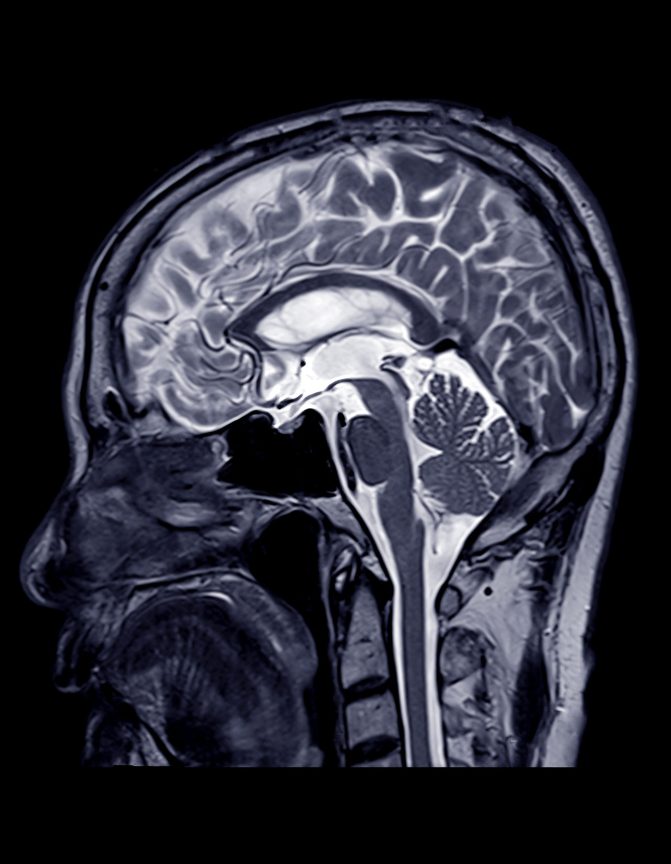

Stenoza carotidiana determina scaderea fluxului sangvin catre creier. Scaderea oxigenarii tesutului cerebral se traduce in ischemie, determinand un accident vascular cerebral. Cel mai important aspect este durata ischemiei – chiar daca dureaza cateva minute, acestea nu trebuie neglijate, pentru ca asa se produce un accident ischemic tranzitor (AIT). Acesta poate fi un semn ce anunta iminenta unui accident vascular cerebral major si poate fi prevenit in majoritatea cazurilor.

Diagnosticarea bolii arteriale carotidiene

Ecografia Doppler cervico-cerebrala

Este o metoda nedureroasa, neinvaziva, care nu prezinta contra-indicatii, reproductibila si care poate evidentia o stenoza carotidiana in 99% din cazuri.

Examinarea angio-CT/angio-IRM

Este o metoda de a doua intentie in cazul in care ultrasonografia cervicocerebrala nu reuseste sa stabileasca cu certitudine gradul de stenoza.